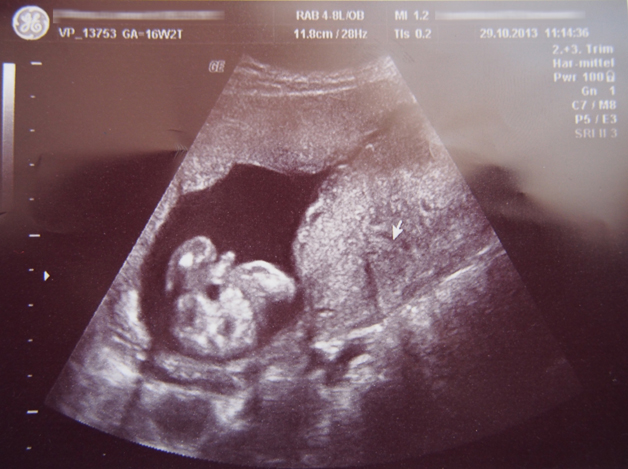

Hey everyone I just wanted to post an update with my 16 week ultrasound. Doctor got a shot of the private area :)

Attachment 15083